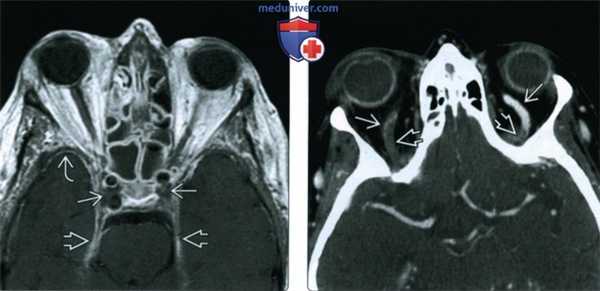

(Слева) При аксиальной МРТ Т2 ВИ у пациента с ХРС определяется снижение пневматизации левой верхнечелюстной пазухи. Содержимое в центре пазухи отчасти гипоинтенсивно из-за малого количества воды и большого количества белка. По периферии определяется воспаленная гиперинтенсивная слизистая оболочка.

(Справа) При аксиальной MPT DWI у этого же пациента определяется диффузное повышение интенсивности сигнала в левой верхнечелюстной пазухе, заполненной содержимым. Определяется рестрикция диффузии, наиболее выраженная в центре.

• Т1ВИ:

о Утолщенная слизистая оболочка изоинтенсивна мягким тканям

о Интенсивность сигнала в содержимом зависит от количества воды и белка:

- Чем больше белка, тем выше интенсивность сигнала (Т1)

• Т2ВИ:

о Слизистая оболочка обычно гиперинтенсивна

о Содержимое пазухи может быть гиперинтенсивным (↑ воды) или гипоинтенсивным (↓ воды, «сухое» содержимое)

о Утолщение стенок пазухи очевидно на MPT (Т2 ВИ)

• Т1ВИ С+:

о Типичное контрастное усиление слизистой оболочки

о Контрастирование не требуется в неосложненных случаях

(Слева) На аксиальной МРТ (Т2 ВИ) у пациента с ХРС определяется нарушение пневматиза-ции левой верхнечелюстной пазухи. Секрет в центре гипоинтенси-вен вследствие высокого содержания воды и малого количества белка. Воспаленная слизистая оболочка на периферии гиперинтенсивна.

(Справа) На аксиальной MPT (DWI) у этого же пациента определяется тотальное повышение интенсивности сигнала в секрете, заполняющем левую верхнечелюстную пазуху (ограничение диффузии), наиболее выраженное в центре.